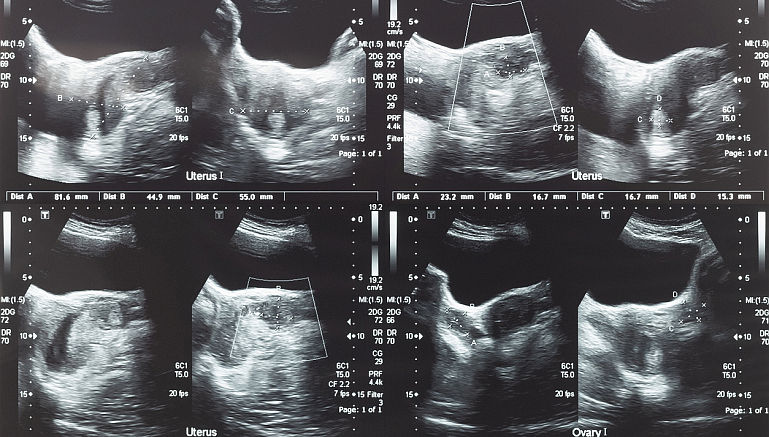

• Ecografia: Ecografia este un test neinvaziv si usor de realizat, cu valoare diagnostica mare. In functie de fiecare pacienta, ecografia poate fi realizata transabdominal sau transvaginal.